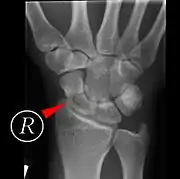

Fractures of the scaphoid are the most common of the carpal bone injuries, because of its connections with the two rows of carpal bones.[1]:177

The scaphoid can be slow to heal because of the limited circulation to the bone. Fractures of the scaphoid must be recognized and treated quickly, as prompt treatment by immobilization or surgical fixation increases the likelihood of the bone healing in anatomic alignment, thus avoiding mal-union or non-union.[5] Delays may compromise healing. Failure of the fracture to heal ("non-union") will lead to post-traumatic osteoarthritis of the carpus.[1]:189 One reason for this is because of the "tenuous" blood supply to the proximal segment.[2] Even rapidly immobilized fractures may require surgical treatment, including use of a headless compression screw such as the Herbert screw to bind the two halves together.

Healing of the fracture with a non-anatomic deformity (frequently, a volar flexed "humpback") can also lead to post-traumatic arthritis. Non-unions can result in loss of blood supply to the proximal pole, which can result in avascular necrosis of the proximal segment.

Scaphoid fractures may be difficult to diagnose via plain x-ray, so repeat x-ray may be used at a later date, or cross-sectional imaging via MRI or CT scan.[5]